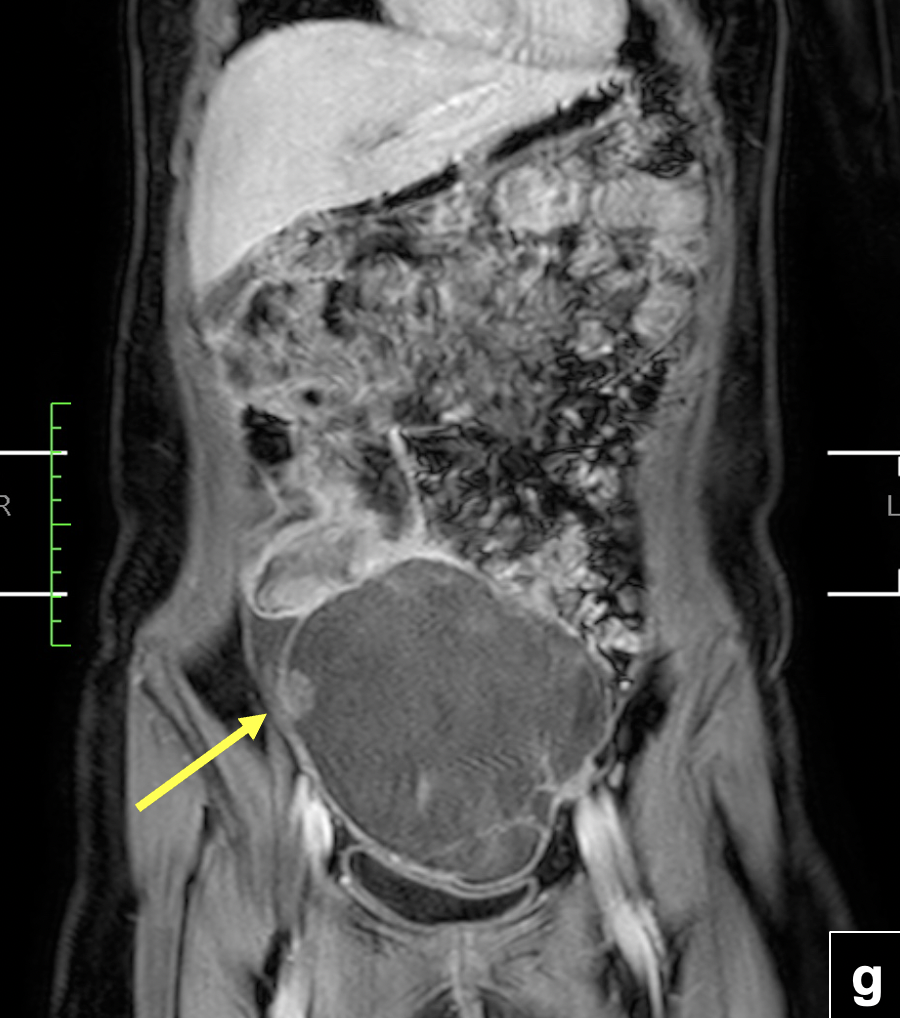

RM de abdomen y pelvis: (f) Secuencias T2 sagital. Se observa tumor solido de íleon distal (flecha) con componente quístico tabicado en hipogastrio (cabeza de flecha). Se visualiza ovario derecho de morfología conservada (asterisco). (g) Secuencia T1 FSE con Gadolinio en plano coronal. Masa quística hipogástrica con tabiques e imagen nodular periférica que realza con el uso de contraste (flecha). Efecto de masa intrabdominal visualizado por el desplazamiento hacia inferior de la pared vesical.Secuencias de pelvis axial en difusión (h,j) y mapa ADC (i,k), que demuestra restricción a la difusión de protones del componente solido del tumor de íleon en estudio y del componente sólido periférico de la masa quística hipogástrica (flecha y cabeza de flecha).